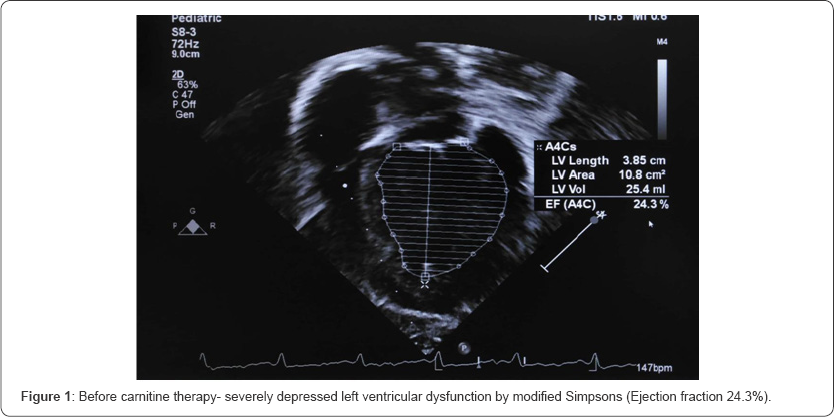

Her initial echocardiogram revealed severe depressed LV dysfunction- Ejection Fraction (EF) by modified Simpsons {24.3%}, M mode EF {24.2%} (Figure 1 &2). In relation to her hypertension related to end-stage renal failure, she is maintained on angiotensin-converting enzyme inhibitors. Further, she was investigated for carnitine levels which confirmed secondary carnitine deficiency (Table 1). After the 6 months trial of 20mg/kg of intravenous carnitine for 5 times a week (end of dialysis) leads to remarkable improvement in IH episodes and cardiac function. Her repeated echocardiogram revealed improved LV function- modified Simpsons {54.1%}, M mode EF {50.4%} (Figure 3 & 4).